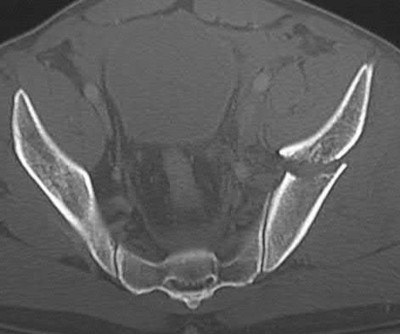

Figure C is an axial CT scan of a lateral compression type 3 (LC3) pelvic ring injury.

Classically, LC3 injuries demonstrate an ipsilateral lateral compression and a contralateral APC (windswept pelvis) fracture pattern. The most common mechanism of injury in these cases is a rollover MVC or pedestrian vs. auto. LC1 injuries are characterized by an oblique or transverse ramus fracture and ipsilateral anterior sacral ala compression fracture, while LC2 injuries consist of a rami fracture and ipsilateral posterior ilium fracture dislocation (crescent fracture). While LC1 injuries can often initially be managed conservatively with protected weight-bearing and close observation, LC2 and LC3 pelvic ring injuries are almost universally operative.

Pennal et al. discuss a radiologic technique for assessing the forces producing pelvic disruption and its use in logically classifying pelvic injury. Based on this radiologic assessment and along with some biomechanical studies, they propose a classification system involving three major forces producing injury that can also be helpful in the management of these patients.

Young et al. performed a retrospective analysis of the plain radiographs of 142 cases of pelvic fractures and identified four patterns of force that presented with distinctive, recognizable radiographic appearances. They describe a classification system for pelvic fractures based on radiographic and clinical findings that correlates with associated injury to soft-tissue structures and enables the surgeon to begin corrective procedures rapidly.

Incorrect Answers:

Answer 1: This represents a lateral compression type 2 injury. Answer 2: This represents a lateral compression type 1 injury.

Answer 4: This represents an anterior posterior compression type 2 injury. Answer 5: This represents an anterior posterior compression type 3 injury.